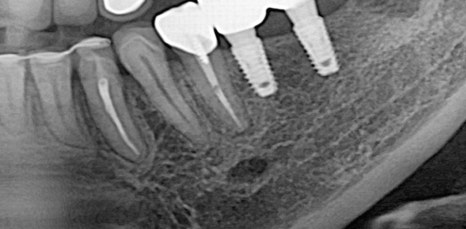

하지만 임플란트 시술을 튼튼하고 안전하게 하기 위해서는 무엇보다 잇몸뼈의 양, 두께 즉, 잇몸 상태가 매우 중요한 부분이었어요. 뿌리 역할을 하는 픽스처의 길이는 다양한 사이즈가 있지만 평균적으로 최소 8mm 이상이므로 잇몸 뼈의 길이가 8mm가 되지 않는 상태로 임플란트를 식립하게 된다면 픽스처가 잇몸을 뚫고 나가게 되어 구멍이 생기고 고정이 되기 어려웠어요. 그렇기 때문에 잇몸 뼈의 양이 부족하면 뼈 이식을 동반한 임플란트 시술이 필요했어요.

특히 위쪽 어금니 쪽이 상실 되어 임플란트 시술을 진행해야 하는데 잇몸 뼈가 부족한 상태라면 추가적으로 상악동거상술을 함께 진행해야 했어요. 상악동이란 코 양옆에 위치하고 있으며 뼈 속에 비어 있는 공기 주머니로 두개골의 무게를 줄여주는 곳이었어요. 상악동은 아주 얇은 막으로 둘러 쌓여 있으며 상악 쪽의 잇몸 뼈가 부족한 상태로 임플란트를 식립 하게 된다면 상악동 막이 찢어지거나 천공이 생길 수 있었어요.

상악동에 천공이 생기게 된다면 염증으로 인해 부작용이 생길 수 있었어요. 그렇기 때문에 환자 개개인마다 크기와 위치가 모두 다른 상악동의 위치와 잇몸 뼈의 두께를 정확히 파악하는 것이 중요했어요. 정밀 검사 후 임플란트를 식립 하기에 잇몸 뼈의 양이 부족하다는 진단이 나오게 된다면 얇은 상악동 막을 들어올려 준 후 필요한만큼의 뼈 이식을 진행해 주는 방법이 상악동거상술이었어요.

이러한 구강 상태를 확인하기 위해서는 여러가지 디지털 입체 장비를 통해 정밀 검사를 진행한 후 정확히 파악하는 것이 중요하며 그에 맞춰 적합한 방법으로 진단한 후 체계적으로 치료 계획을 수립 해야 했어요. 의료진의 진단과 시술 경험에 따라 치료 결과는 크게 달라질 수 있기 때문에 상악동거상술을 동반한 임플란트 시술을 안전하고 성공적으로 마치기 위해서는 치과를 선택할 때 꼼꼼히 따져본 후 치료를 시작하는 것이 바람직한 방법이었어요.

신논현역임플란트에서는 3D 구강스캐너와 CT 등 다양한 전문 장비로 구강상태를 정밀하게 입체적으로 확인하고 환자분과 상담을 통해 상악동거상술의 치료 계획을 세우고 있었어요. 상악동거상술은 치과 치료 중에서도 난이도가 높은 치료에 속하기 때문에 환자분께서는 부담스럽고 두려우실 수 있었어요. 무턱대고 당장 치료를 시작하기 보다는 신논현역임플란트 잘하는 아름드리치과에서는 1:1 맞춤치료를 진행하며 환자분들과 충분한 상담을 통해 궁금증을 해결 해 드리고 통증과 부작용에 대한 우려를 덜어 드린 후 안심하고 진료 받을 수 있도록 의사소통을 활발히 하며 언제나 환자분을 우선으로 생각하며 진료하고 있었어요. 또한 얇은 상악동막이 찢어지거나 구멍이 나지 않도록 섬세하고 전문적인 실력이 뒷받침되어야 상악동거상술의 부작용을 최소화 할 수 있었어요.